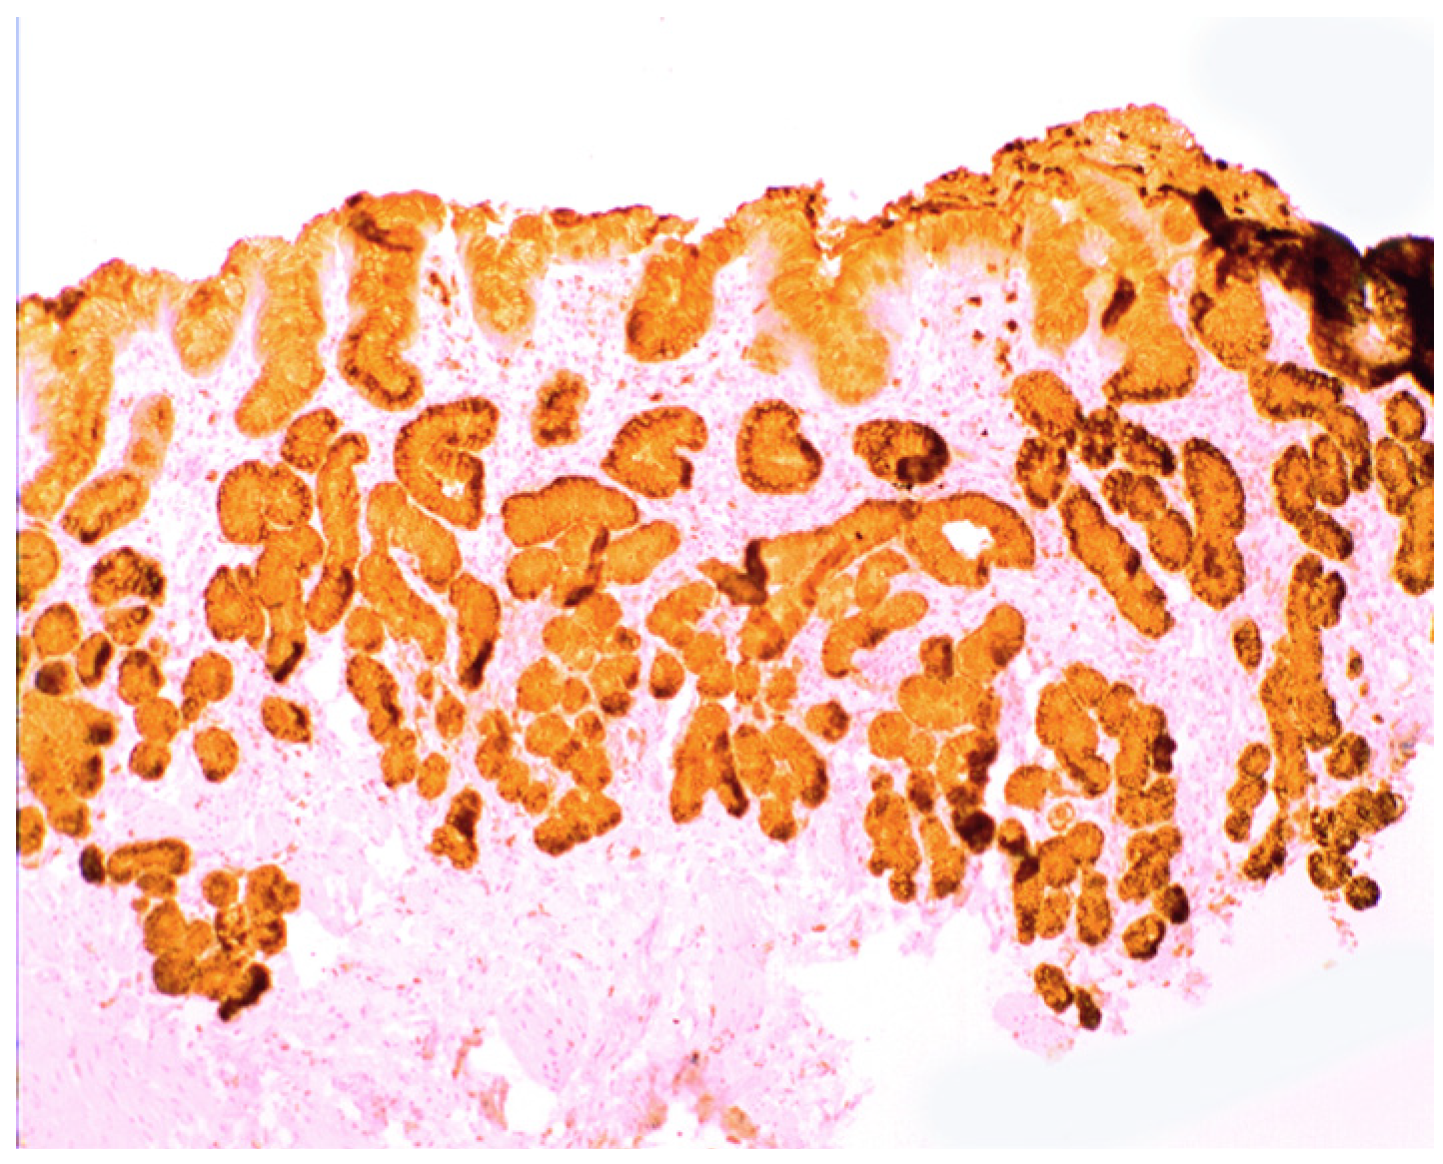

Increased lysozyme immunoreactivity was found In Barrett’s oesophagus; in the surface columnar epithelium, in the columnar epithelium of the pits of the glands (Figure 1), in goblet cells (Figure 2), as well as in Paneth cells in cases with intestinal metaplasia [24].

Figure 1. Barrett’s mucosa (pyloric phenotype) showing lysozyme expression in surface epithelium, foveolar epithelium, and pyloric glands (lysozyme immunostain, ×4).